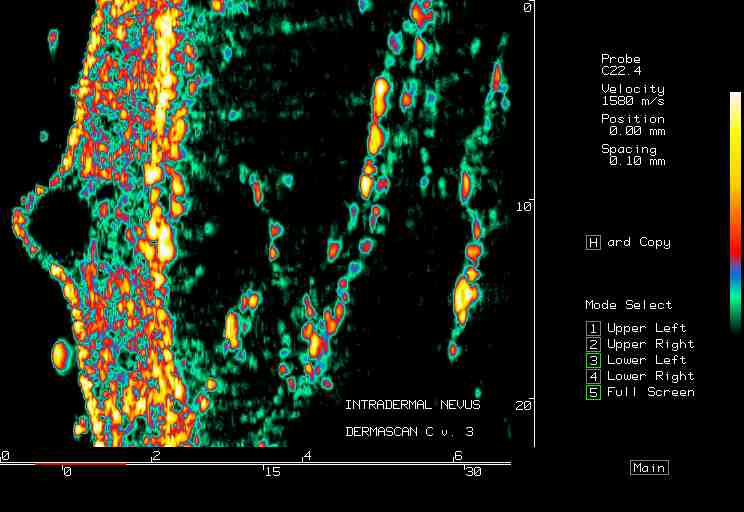

Intradermal nevus |